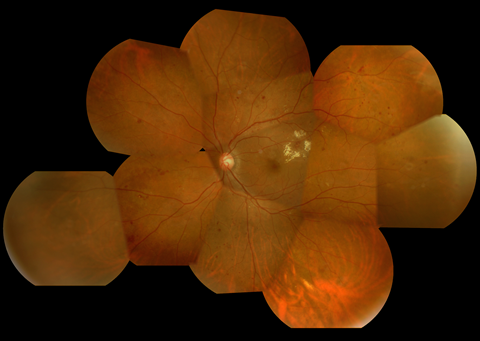

1.単純糖尿病網膜症

| 初期の網膜症 | 高血糖の影響から毛細血管の血管壁が障害され、血管に瘤ができたり、血管壁から血液や血漿成分がしみ出たりすることによって、点状出血や硬性白斑(脂肪やタンパク質の漏出)が生じます。 | この段階では血糖治療、高血圧治療が非常に大切になります。しかし、この段階でも黄斑浮腫が生じている場合には、レーザー治療(網膜光凝固術)や抗VEGF療法の適応になる場合もあります。 |

硬性白斑 |